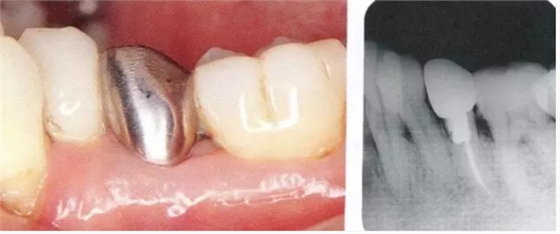

2222.png

▲圖18-1,2

▲圖18-1 左下5佩戴金屬冠,但是由于近遠(yuǎn)中接觸點(diǎn)的位置和大小不合適,導(dǎo)致鼓形間隙基本消失。

▲圖18-2 同部位的X光片??梢钥吹烬l下有牙結(jié)石沉積,并且有牙槽骨吸收現(xiàn)象。